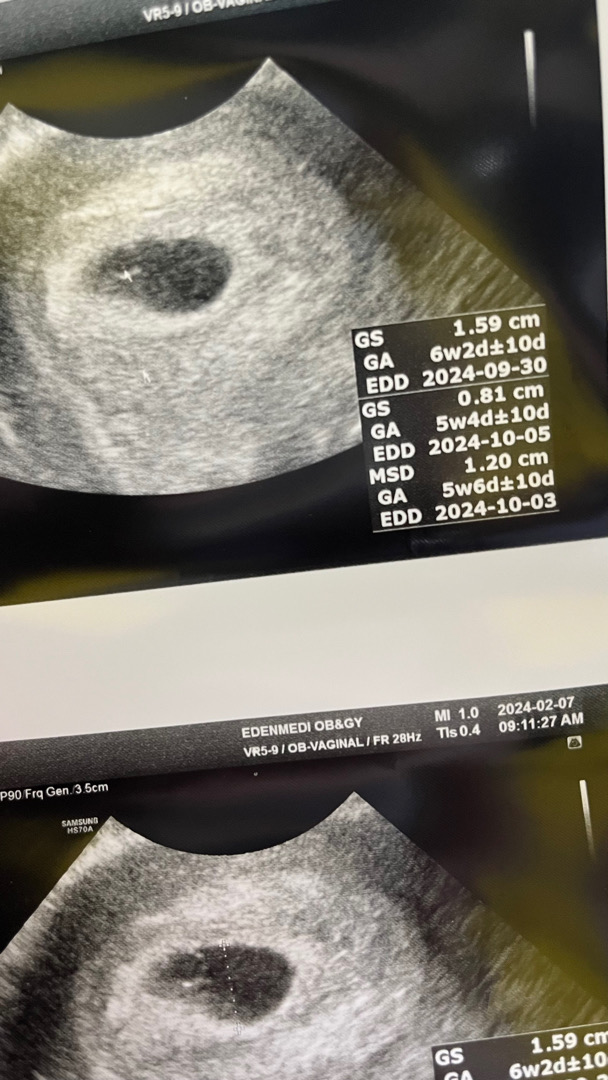

아기집 보고왔어요 ㅎㅎ

12/28일 막생이고 생예 1/27 인데 빨리 눈치채서 23일에 흐린 두줄확인 후 25일 피검 31수치로 임신 확인 받고 피 말리는 2주를 기다려서 아기집 확인했어요!! 근무하던 일을 아직 정리를 못 해서 무리해서 근무 하다보니 걱정이 많았는데 역시 아기는 강하군요! 집을 잘 지어놨더라구요 확인하자마자 기특하고 뭉클하고 그래요,,🩷 다음주에는 심소 들을 수 있다네요 ㅎㅎ 떨려요